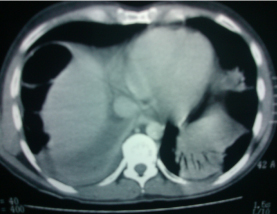

También se solicitó una tomografía computarizada (TAC) simple de abdomen, que reportó esteatosis hepática y pancreatitis Balthazar B (figura 2).